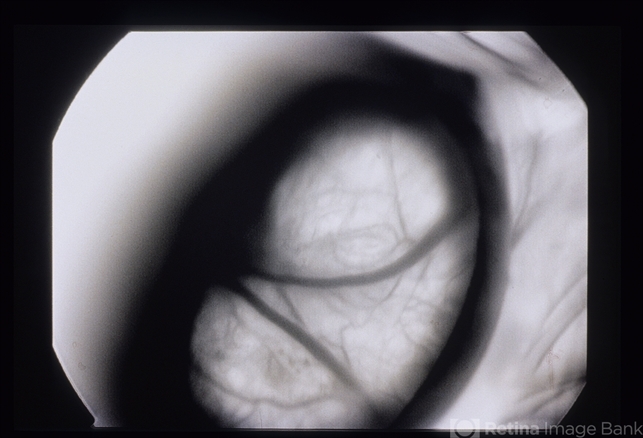

Floaters And Blurred Vision

floaters, blurred vision

A 23 year old white female who presented with floaters and blurred vision in the left eye for 2 weeks.